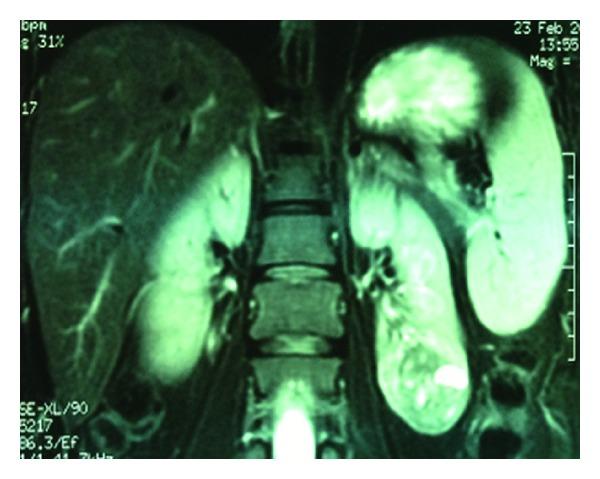

Charts of the initial RANSSs (n = 44), which were performed by a single surgeon, were retrospectively reviewed. R.E.N.A.L. nephrometry system, modified Clavien classification, and M.D.R.D. equation were used to record tumoral complexity, complications, and estimated glomerular filtration rate (eGFR), respectively. Outcomes of the clamped (group 1, n = 14) versus off-clamp (group 2, n = 30) RANSSs were compared.

The difference between the two groups was insignificant regarding mean patient age, mean tumor size, and mean R.E.N.A.L. nephrometry score. Mean operative time, mean estimated blood loss amount, and mean length of hospitalization were similar between groups. A total of 4 patients in each group suffered 11 Clavien grade ≥ 2 complications early postoperatively. Open conversion rates were similar. The difference between the 2 groups in terms of the mean postoperative change in eGFR was insignificant. We did not encounter any local recurrence after a mean follow-up of 18.9 months.